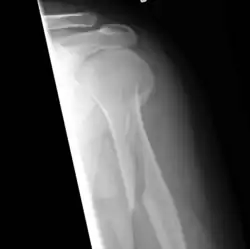

An x-ray image of a spiral fracture to the left humerus (upper arm bone) of a 27-year-old male. The injury was sustained during a fall.

A spiral fracture (a.k.a. torsion fracture) is a bone fracture occurring when torque (a rotating force) is applied along the axis of a bone.[1] Spiral fractures often occur when the body is in motion while one extremity is planted. For example, a spiral fracture of the tibia (the shinbone) can occur in young children when they fall short on an extended leg while jumping. This occurrence is known as "toddler's fracture". Spiral fractures are also recognized as being suspicious in very young children since to obtain a fracture of this sort requires forceful twisting or jerking of the limbs. Child abuse (physical abuse) and certain conditions such as osteogenesis imperfecta (OI) are considered differentials when identifying spiral or torsion fractures.[2]